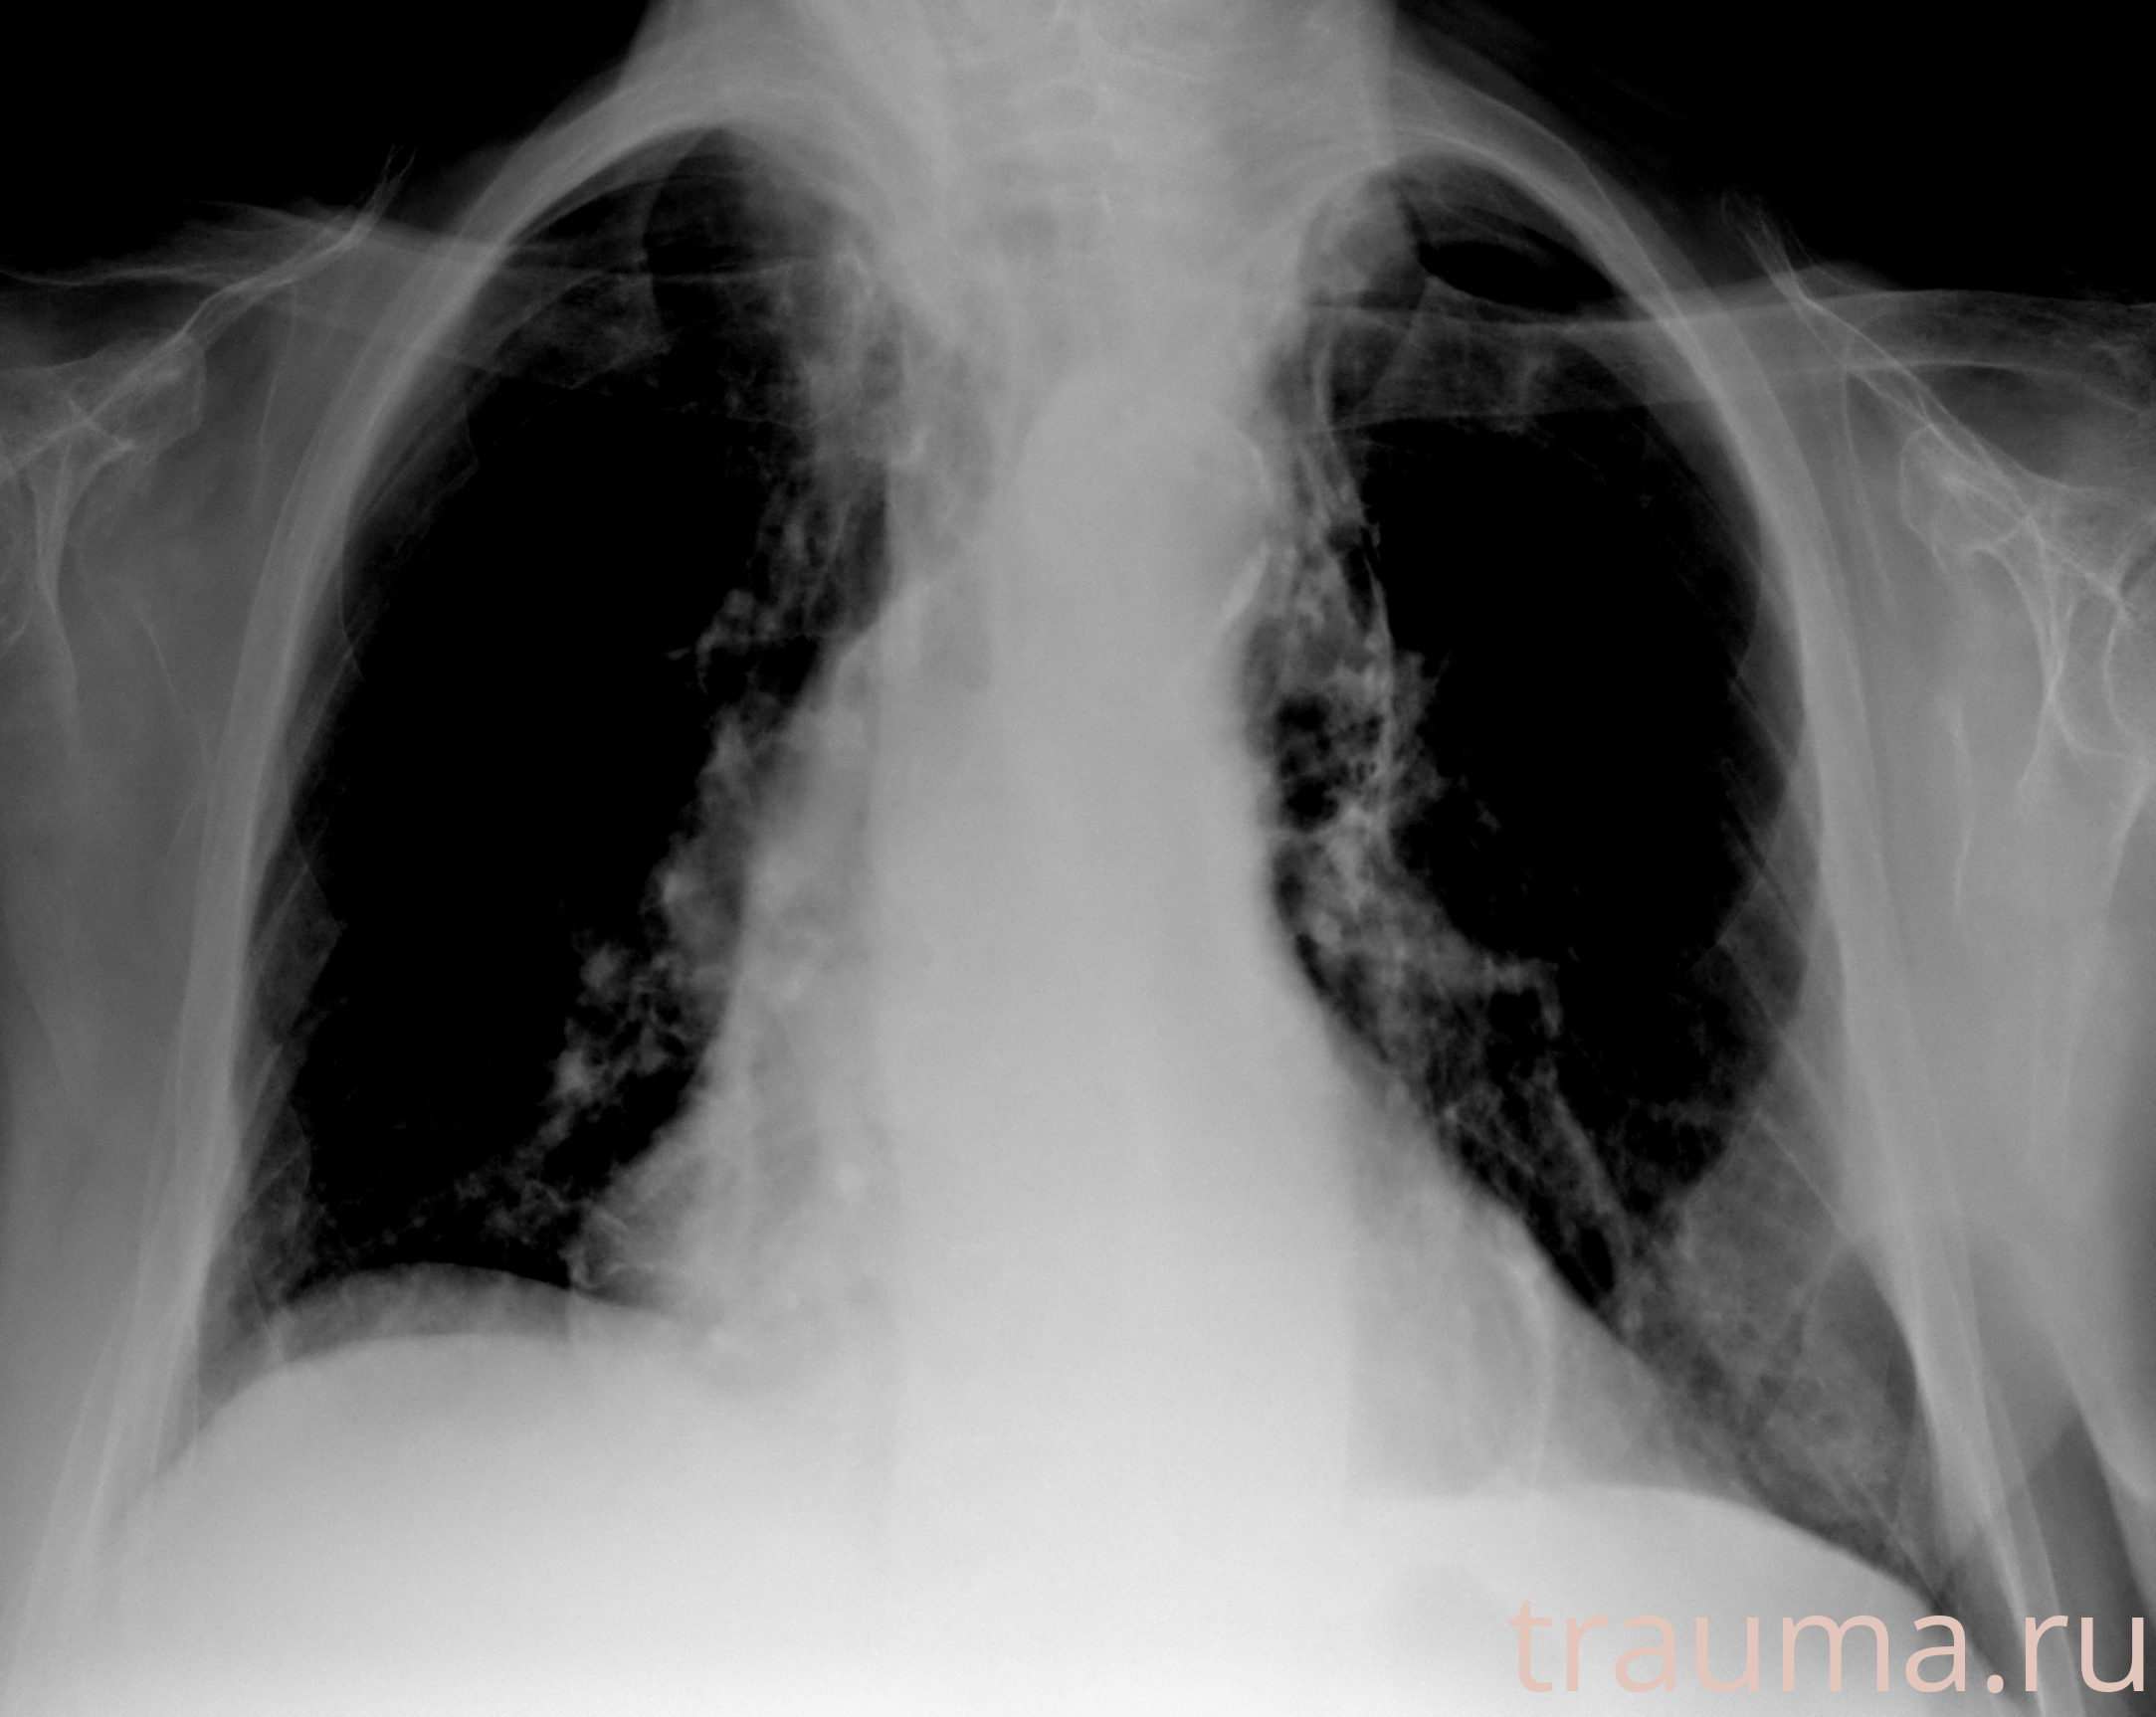

Рентгенограммы

Рентген на дому: по вашему адресу приезжает врач-рентгенолог, травматолог-ортопед с мобильным рентгеновским аппаратом, проводит диагностику травмы или заболевания, делает необходимые рентгенограммы, дает рекомендации по дальнейшему лечению. Получить качественные снимки в домашних условиях возможно благодаря уникальной методике, разработанной МосРентген Центром для института  Склифосовского

Яркость: 1   Контраст: 1   Инвертировать: 0 Увеличение: 1

Перетаскивайте мышь вверх/вниз для контраста, влево/право для яркости. Прокрутка колесом изменяет масштаб. Нажмите Сбросить для возврата к исходному изображению. При увеличении держите мышь в той области, которую хотите рассмотреть.